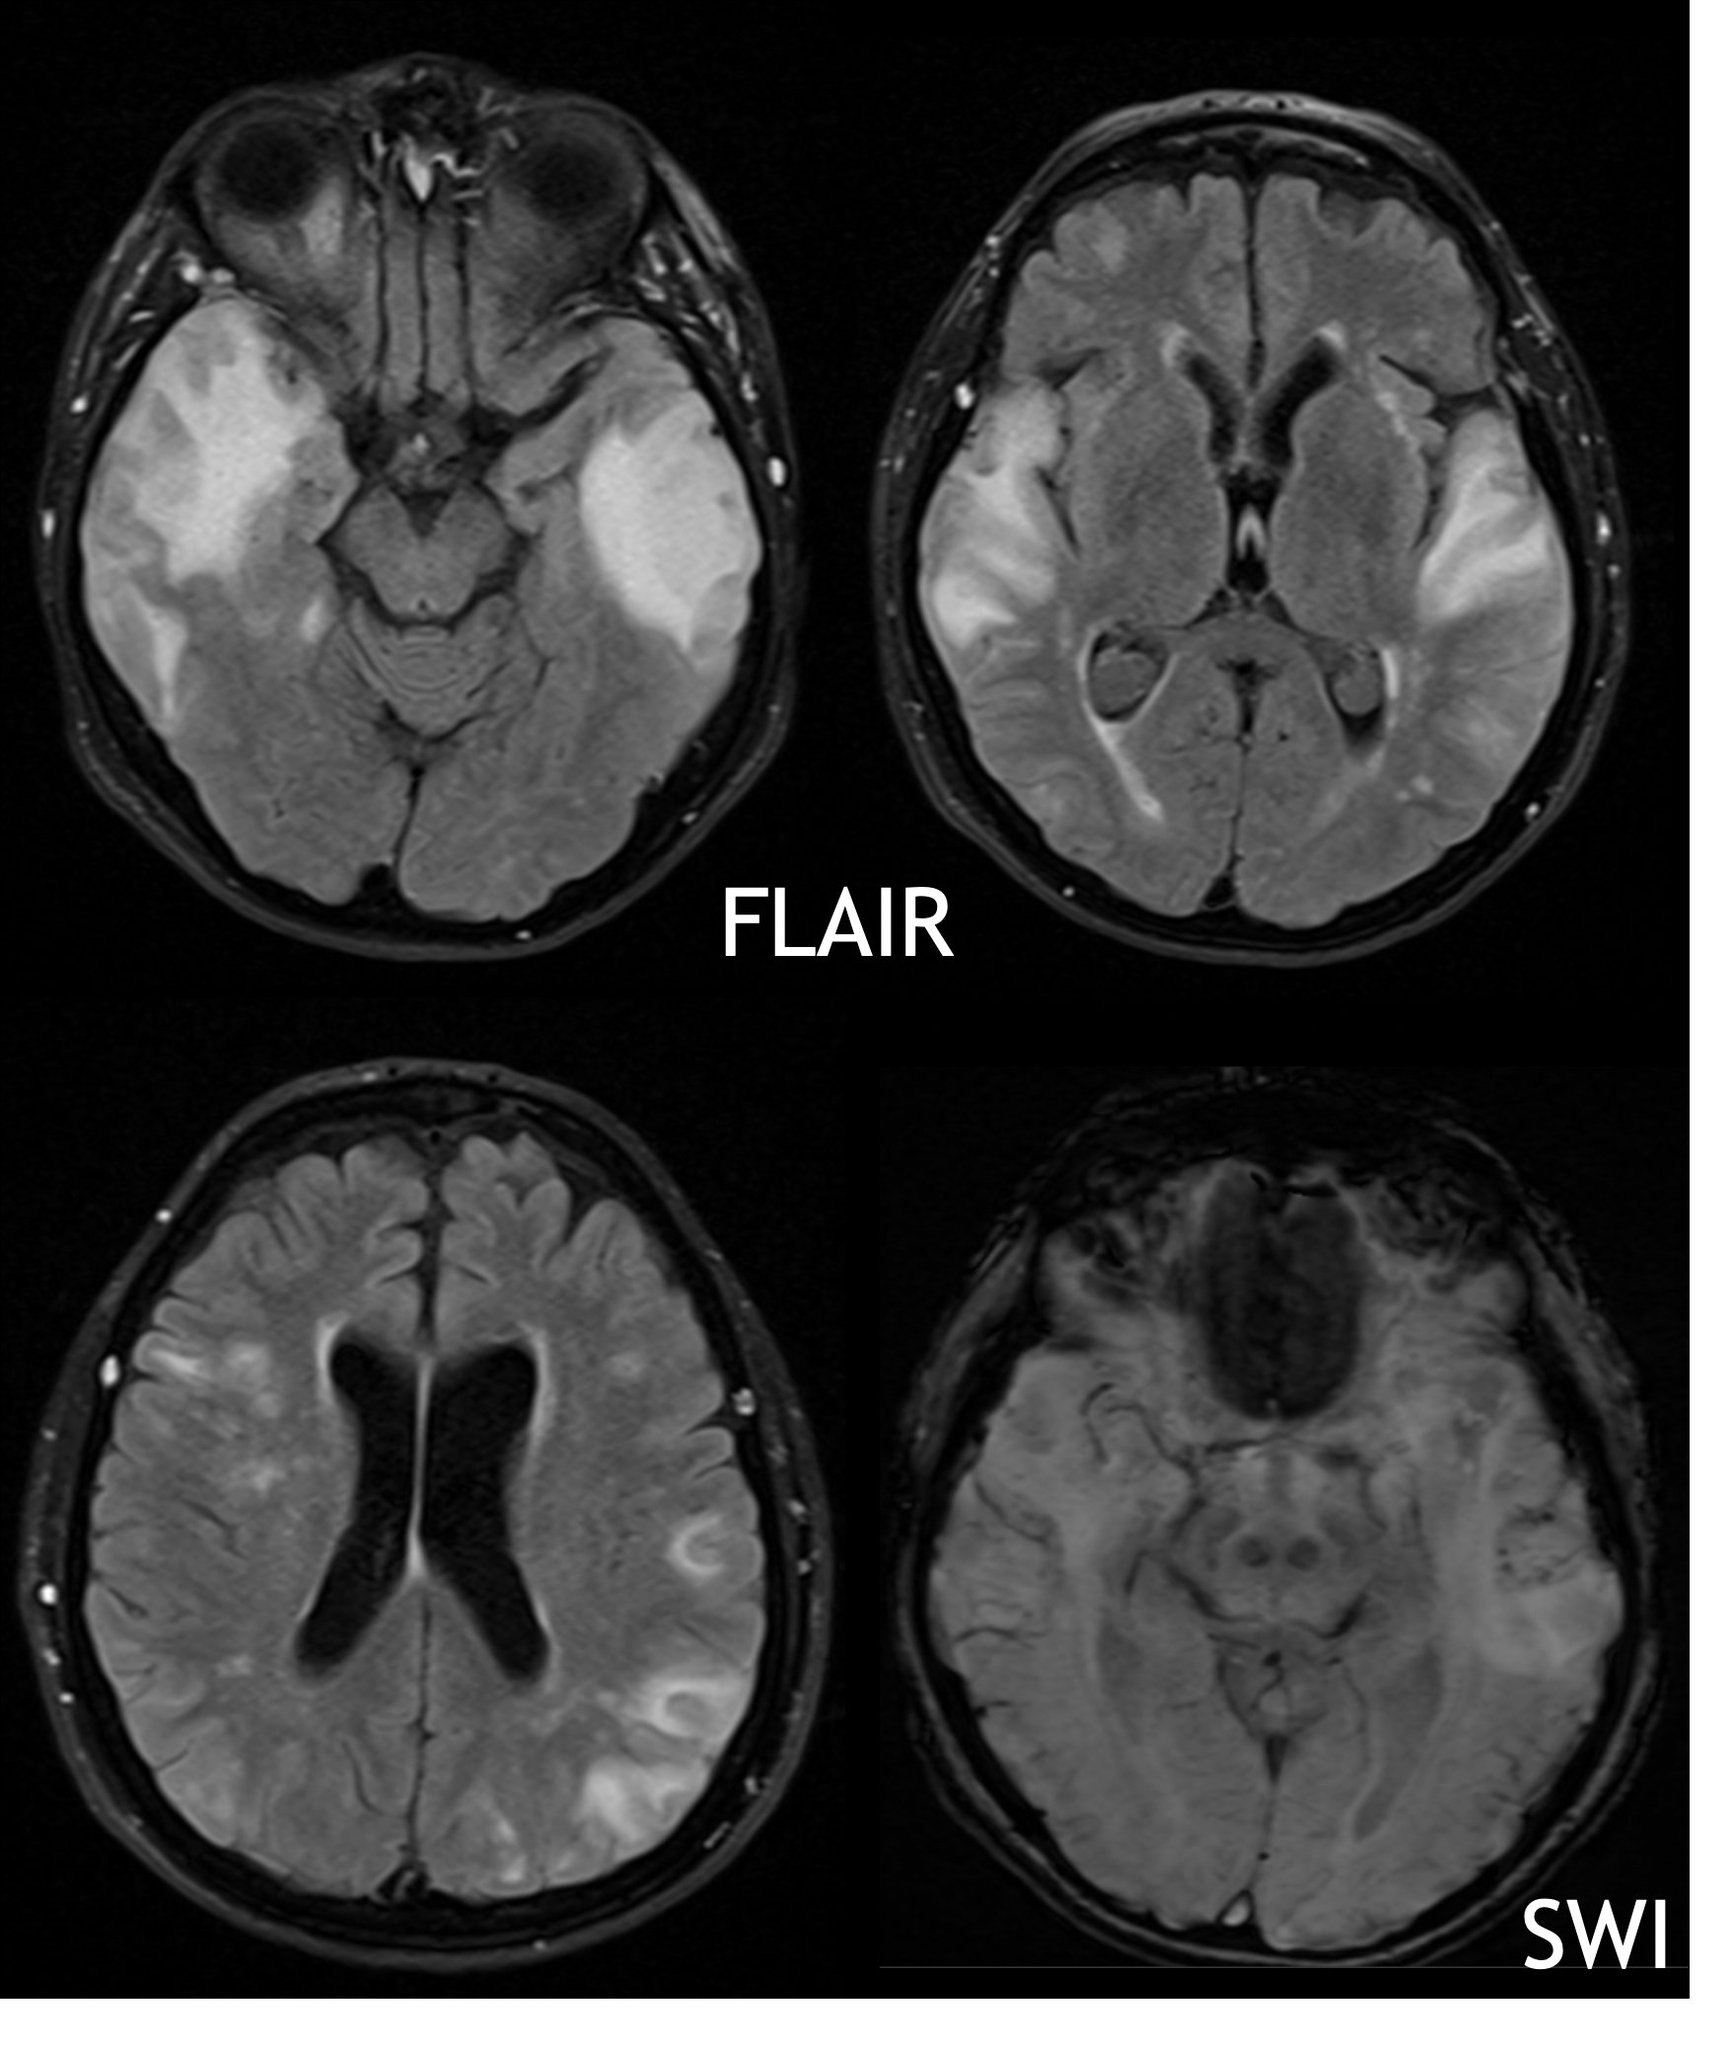

Andreas Charidimou MD, PhD on Twitter "⚡️🚨Patient with mild Headache After Covid Monoclonal Antibodies appen during and after infusion with monoclonal antibody treatment. Tell your healthcare provider right away if you get. — several hypotheses have been proposed on the pathophysiology of headache in the context of acute covid. Headache After Covid Monoclonal Antibodies.